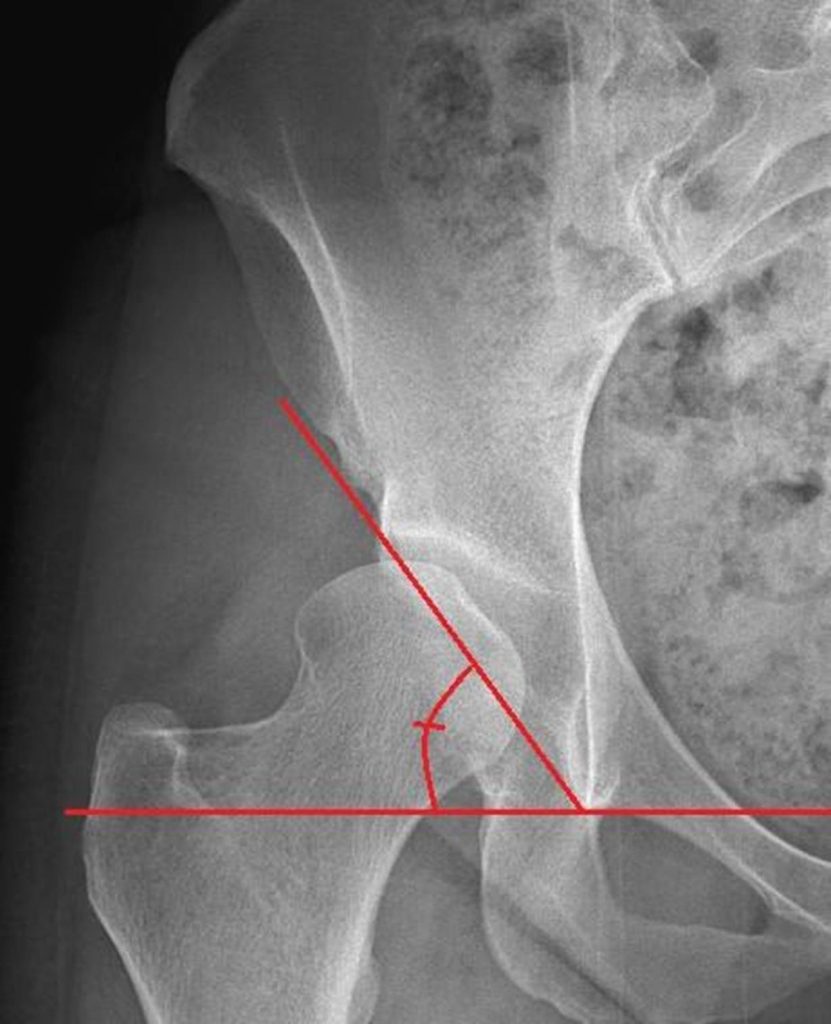

Tonnis Angle

The Tonnis angle measures the upward slope of the hip socket. A slope between 0-10 degrees is normal and allows for even loading across the joint.

>10 degrees: a steep slope may be seen with dysplasia. This increases load/stress placed across smaller parts of the joint, and can cause pain and damage to the cartilage.

< 0 degrees: a shallow slope may be seen with FAI. This can cause pain and may limit hip range of motion.

– A slope between 0-10 degrees is normal and allows for even loading across the joint.